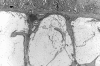

Figure 1.

Fissure (arrowhead) in cecum of IL-10−/− mouse infected with E. faecalis for 20 weeks. H&E; original magnification, ×100.